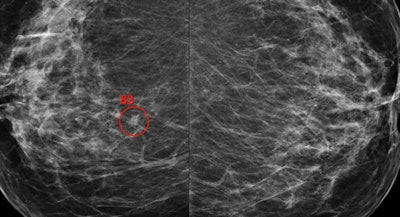

One-view breast tomosynthesis versus two-view mammography in the Malmö Breast Tomosynthesis Screening Trial (MBTST): A prospective, population-based, diagnostic accuracy study. Zackrisson S et al, Lancet Oncology, November 2018.

This Swedish study included almost 15,000 women screened over a period of five years who first underwent two-view digital mammography screening and then one-view digital breast tomosynthesis (DBT) with reduced compression during another visit. DBT with a single view detected over a third more (34%) breast cancers than traditional mammography, and most of the breast cancers were invasive cancers.

DBT demonstrated a higher sensitivity at 81.1% versus 60.4% for digital mammography, according to lead author Dr. Sophia Zackrisson, an associate professor at Lund University and a radiologist at Skåne University Hospital in Malmö.

To simplify breast cancer screening using DBT, the prospective, population-based Malmö trial investigated single-view DBT (mediolateral oblique view) compared with conventional two-view digital mammography.

"This strategy minimizes the radiation dose to women undergoing breast cancer screening and reduces the extent of screen-reading compared with dual-imaging methods," Zackrisson and colleagues wrote. "If supported by cost-effectiveness studies, one-view digital breast tomosynthesis warrants consideration as the preferred breast cancer screening method in the future."